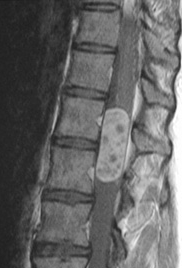

Vücudumuzu dik tutan bel kemiği (omurga) bazan eğrilikler gösterir. Çok genç yaşlarda başlayabilen e ...

Sırtımızda hemen hemen boyun bölgesinden başlayıp kalçamızdan daha aşağıya kadar uzanan ve omurilik ...

Omurilik tümörleri, omuriliği kaplayan koruyucu kılıfların arasında ya da kılıfın yüzeyinde gelişeb ...

Spinal metastazların tedavisinde cerrahinin amacı en az invaziv yöntem kullanarak maksimum derecede ...

Perkütan vertebra cisminin sağlamlaştırılması hem ağrıyı kontrol hem de vertebra cisminin dayanıklıl ...